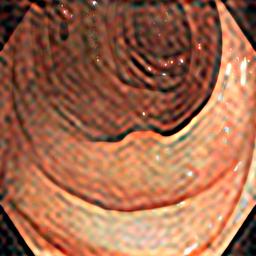

As Fig. 2(c) shows, background inference (shadows) is introduced by the Fourier-Transform-Based domain generalization. In our ICASSP-2024 study [25], we applied soft-thresholding (ST) filtering to minimize background interference in retinal fundus image segmentation. Soft-thresholding, a widely recognized technique in signal processing and statistical estimation, promotes sparsity and enhances data quality [26, 27]. By applying a threshold to the DFT coefficients, it effectively reduces noise and irrelevant details while preserving essential features. The soft-thresholding function operates for a given threshold as follows:

where is the input and is the threshold value. However, when we applied the same domain generalization method [25] on the polyp dataset, we notice that the soft-thresholding function enhances noisy patterns while eliminating the shadows caused by the target background, as Fig. 2(d) present. This is because the soft-thresholding function shrinks all coefficients (both large and small) toward zero. This introduces bias in the retained large coefficients, potentially distorting important features.

As Fig. 2(d) reveals, applying hard thresholds removes shadows caused by the amplitude swapping without producing noisy patterns, but it may smooth the synthetic images.